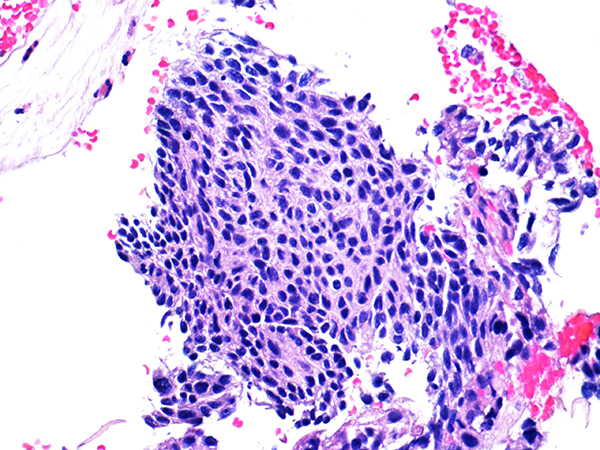

![]() Case 2

Soft Bx CIN 2 10x - Low Power |

Soft Bx CIN 2

40x - High Power